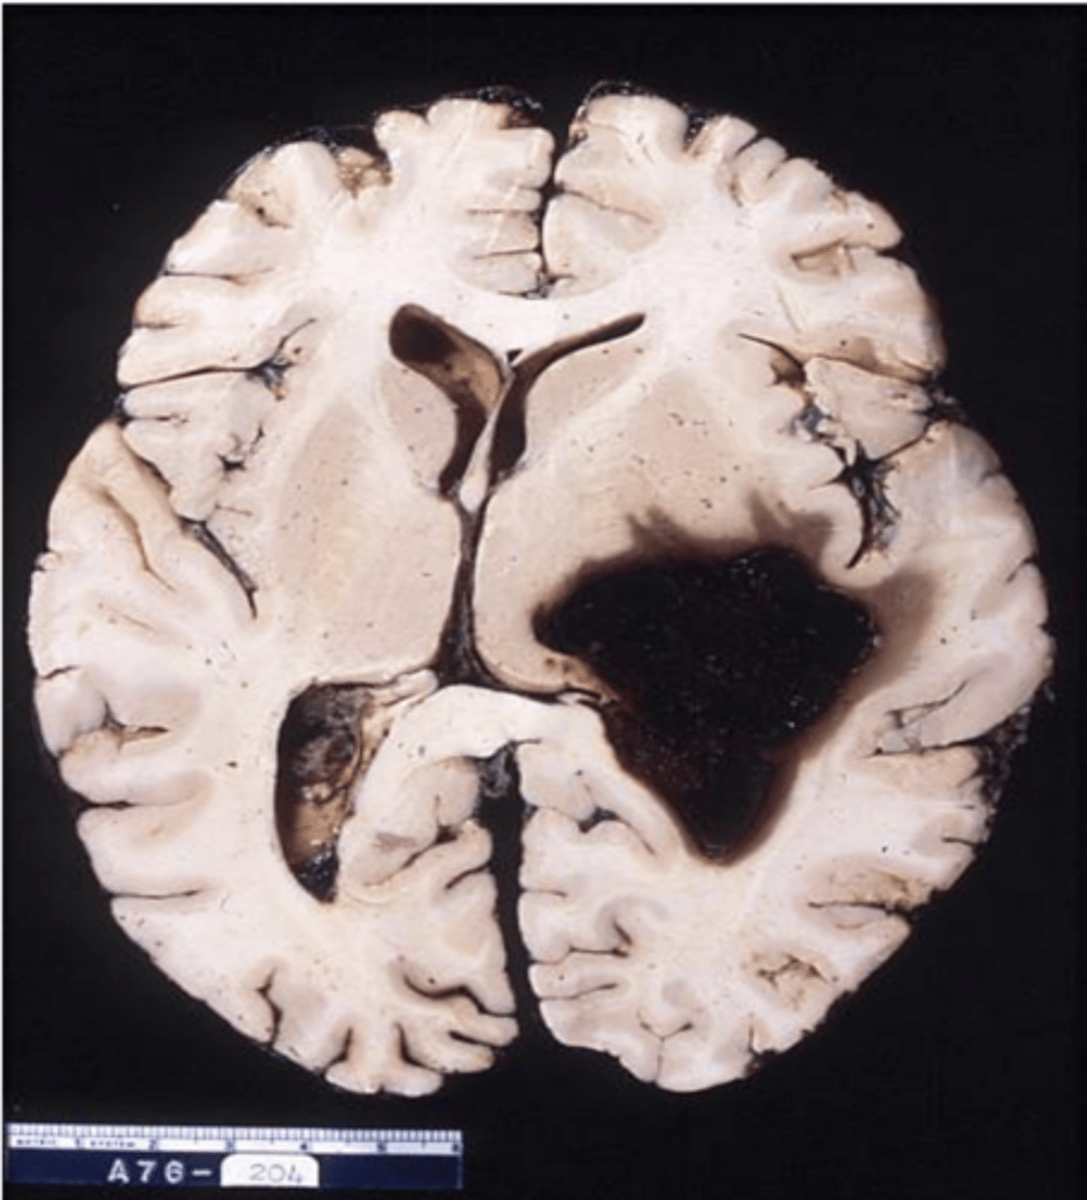

smaller lacunar infarct

old MCA infarct -> not the cause of death, but can see the changes/damage post-mortem from a previously experienced MCA infarct